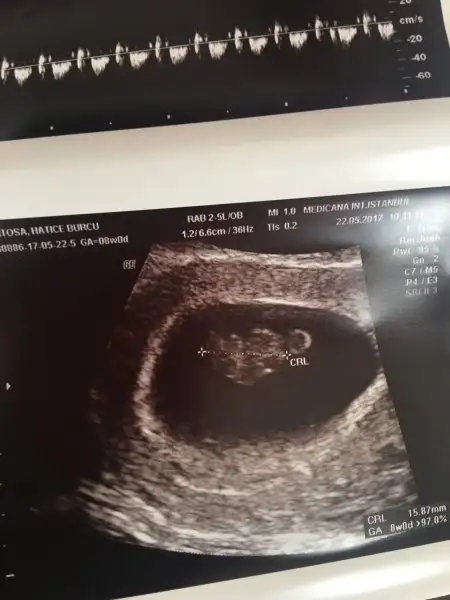

kızlarrr benim ultrasonumada bakın sizce ne olabilirrr??

Eklentiler

• IMG_5037.webp

Kızlar başka doktona gittim çok şükür gördüm kalbide çok güzel atıyo. Kol bacağı çıkmış çok komik ya:KK48: acayip duygulandım böyle bi duygu olamaz:cry:. 2 cmmiş boyu. Sata göre 9+5 ama ultrasonda 8+4 . Geç yumurtlama olduğu için O yüzden son adet tarihimi 8 gün ileri sardı. Birde fitil verdi. Sonunda kan tahlillerimde yapıldı.birde kesenin altında kanama varmış ama önemli bişey değil dedi